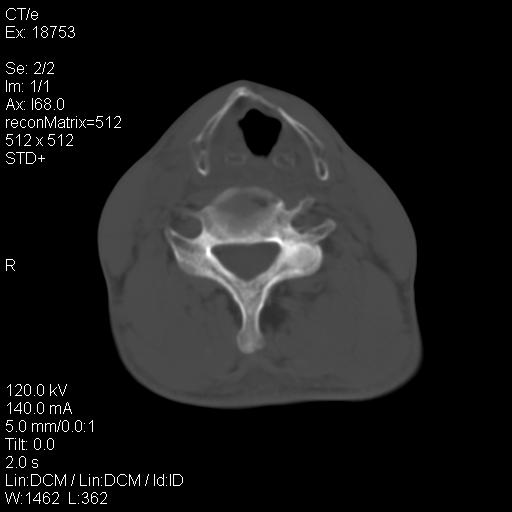

标题: CT21693:男 58岁 右侧咽部疼她2天余 PE:右侧扁桃体肿大 压痛 [打印本页]

标题: CT21693:男 58岁 右侧咽部疼她2天余 PE:右侧扁桃体肿大 压痛

右化脓性扁桃体炎症伴咽后壁脓肿形成.